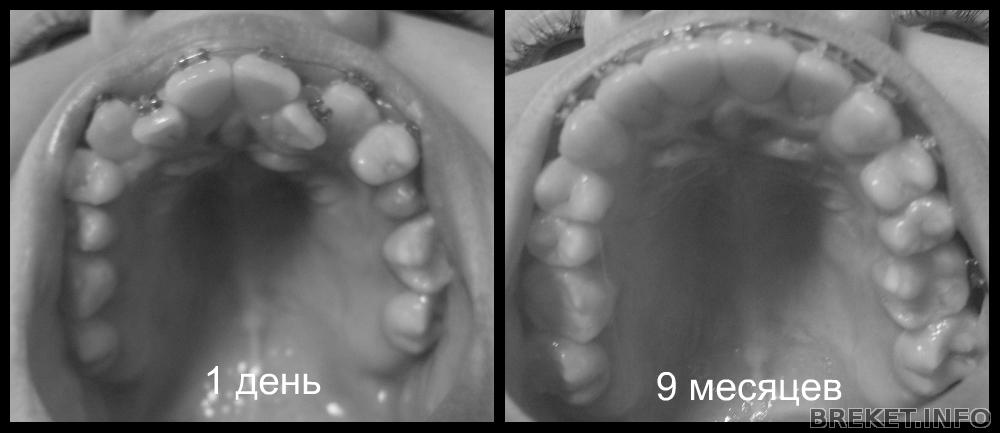

9 месяцев

Медленными шажками подошла к 9 месяцу. Теперь,я знаю,что беременость длиться не долго)

Вот такие результаты:

9 месяцев.jpg

9_vtczwtd.jpg